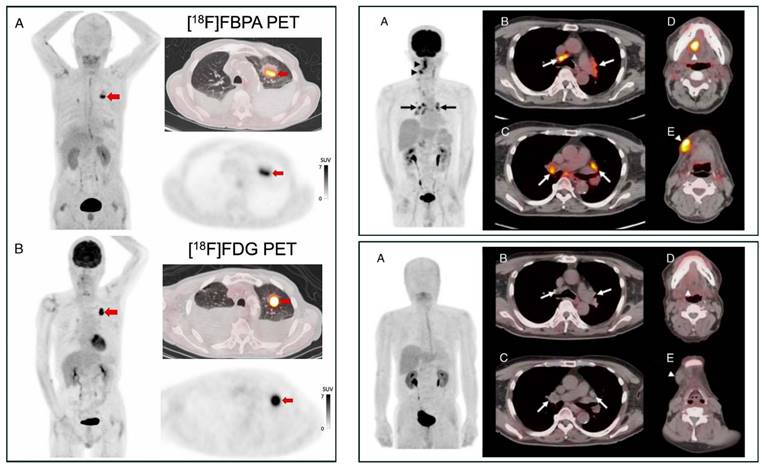

Figure 3

PET MIP and axial PET/CT image comparison between [18F]FBPA and [18F]FDG. Left box: A primary lung squamous cell carcinoma on a 71-year-old man (red arrows, [18F]FDG SUVmax 14.8 and [18F]FBPA SUVmax 7.2). Reproduced as is from [66]. Copyright © 2023, Copyright © 2023 The Author(s). Published by Wolters Kluwer Health, Inc. Originally published under Creative Commons Attribution-Non Commercial-No Derivatives License 4.0 (CCBY-NC-ND license). Right boxes: A tongue cancer and mediastinal sarcoidosis case in a 68-year-old man. The [18F]FDG PET images (upper box) and [18F]FBPA PET images (lower box) were taken ten and eleven days following high-dose brachytherapy for his tongue cancer, respectively. [18F]FDG PET images visualized active inflammation in his mediastinal sarcoidosis (upper box, A-C, arrows) and post-radiation inflammation (upper box, D & E, arrowheads), while no [18F]FBPA uptake in the corresponding area of the mediastinum (lower box, A-C, arrows), tongue, and submandibular region (lower box, D & E, arrowheads). Reproduced as is from [67]. Copyright © 2020, Copyright © 2020 The Author(s). Published by Wolters Kluwer Health, Inc. Originally published under Creative Commons Attribution-Non Commercial-No Derivatives License 4.0 (CCBY-NC-ND license).

[18F]FBPA is claimed as LAT1-specific (Km LAT1 = 197 µM, Km ratio LAT2/LAT1=14), while BPA has much lower LAT1-specificity (Km ratio LAT2/LAT1 = 4.3) [62]. In melanoma, [18F]FBPA is involved in melanogenesis, and thus melanoma lesions have higher [18F]FBPA uptake [57]. Adding the α-methyl group might improve the LAT1 selectivity (this tracer is still in early investigation) [63]. As a LAT1 substrate (subject to bi-directional transport), consequently, [18F]FBPA tumor uptake is generally lower than PET radiotracers whose trapping mechanism within cancer cells, like [18F]FDG. However, [18F]FBPA tumor uptake is about similar to that of [11C]MET [64]. A high-contrast image in [18F]FBPA PET can be obtained earlier than the typical 60 min post-injection scan (Figure 2) [65]. [18F]FBPA PET visualized thoracal and mediastinal malignant lesions with high contrast (Figure 3A) [66]. In benign lesions, [18F]FBPA uptake was consistently low (SUVmax < 2), while [18F]FDG uptake on the same lesions was higher (SUVmax > 5). More importantly, unlike [11C]MET and [18F]FDG, [18F]FBPA does not accumulate in inflammatory tissues, including post-radiation necrotic lesions (Figure 3B) [67].